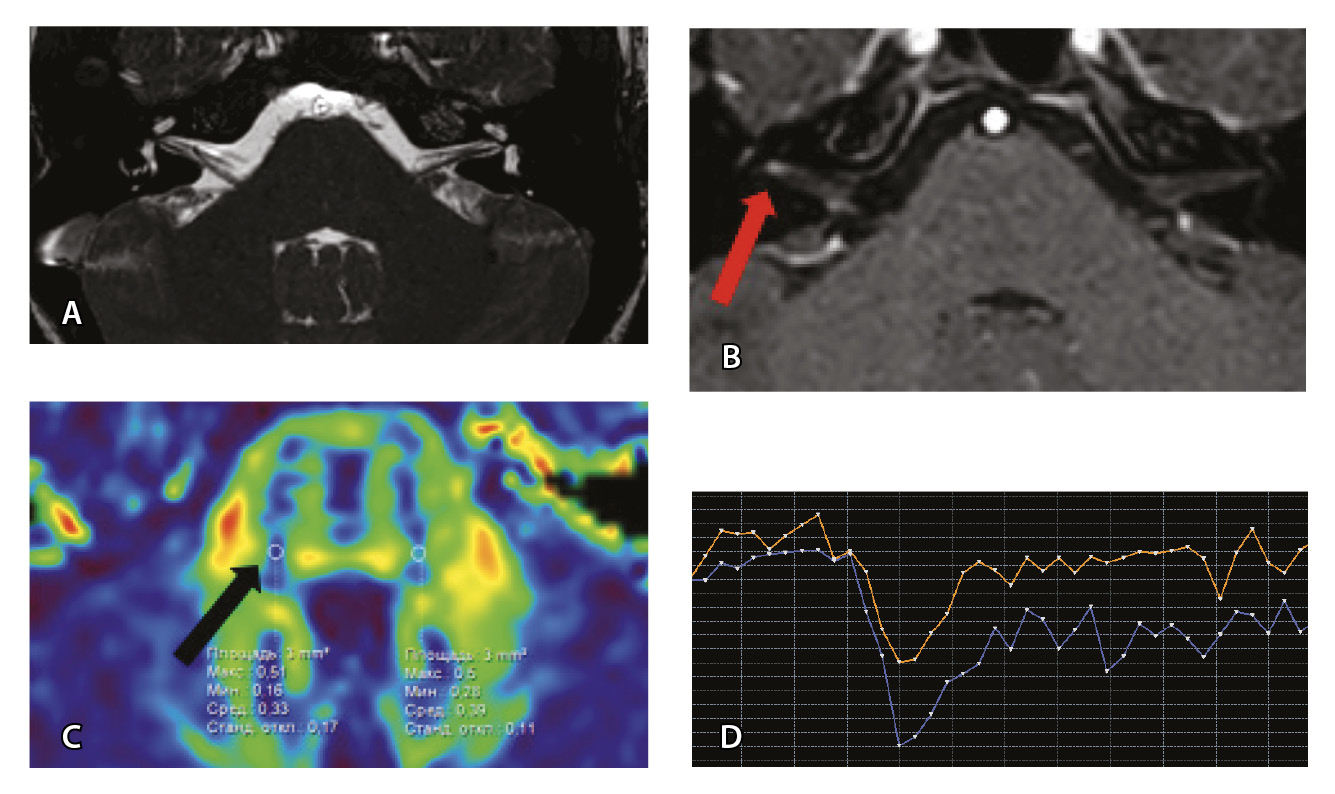

Рис. 3. Пациент Г. Магнитно-резонансная томография (МРТ) головного мозга: А – прицельная T2-SSFP на область мосто-мозжечкового угла; Б – Т1-взвешенное изображение с контрастным усилением; В – диффузионно-тензорная МРТ (фракционная анизотропия); Г – Т2*-перфузия (здесь и далее графики перфузии отражают зависимость повышения интенсивности МР-сигнала, то есть накопления контрастного вещества (вертикальная ось) от времени (горизонтальная ось), тем самым иллюстрируя основные показатели перфузии – relCBV, TTP, MTT). На изображениях T2-SSFP патологические изменения на уровне прохождения лицевых нервов во внутренних слуховых проходах (А), повышенное накопление вещества корешками лицевых нервов (Б) не определяются. Показатели фракционной анизотропии (В) и Т2*-перфузии (Г) на уровне моторных ядер лицевых нервов симметричны

Рис. 6. Пациентка З. Магнитно-резонансная томография (МРТ) головного мозга: А – прицельная T2-SSFP на область мосто-мозжечкового угла; Б – Т1-взвешенное изображение с контрастным усилением; В – диффузионно-тензорная МРТ (фракционная анизотропия, ФА); Г – Т2*-перфузия. На изображении T2-SSFP патологические изменения на уровне прохождения лицевых нервов во внутренних слуховых проходах не определяются (А). При контрастировании отмечается накопление контрастного вещества правым лицевым нервом во внутреннем слуховом проходе (Б, красная стрелка). На уровне моторных ядер лицевого нерва в заднем отделе варолиевого моста на изображениях ФА на стороне поражения отмечается минимальное уменьшение показателя ФА до 0,33 (В, черная стрелка) и признаки гипоперфузии справа (Г, оранжевый график) по сравнению с контралатеральной стороной (Г, синий график). Данный пример демонстрирует типичные изменения при мультипараметрической МРТ у пациента с параличом Белла